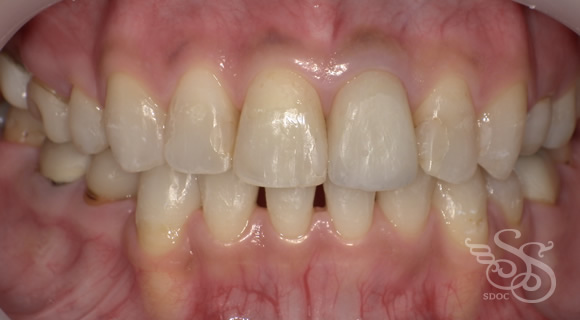

久しぶりに会った友人に「整形した?」と言われた患者さま

術前

術後